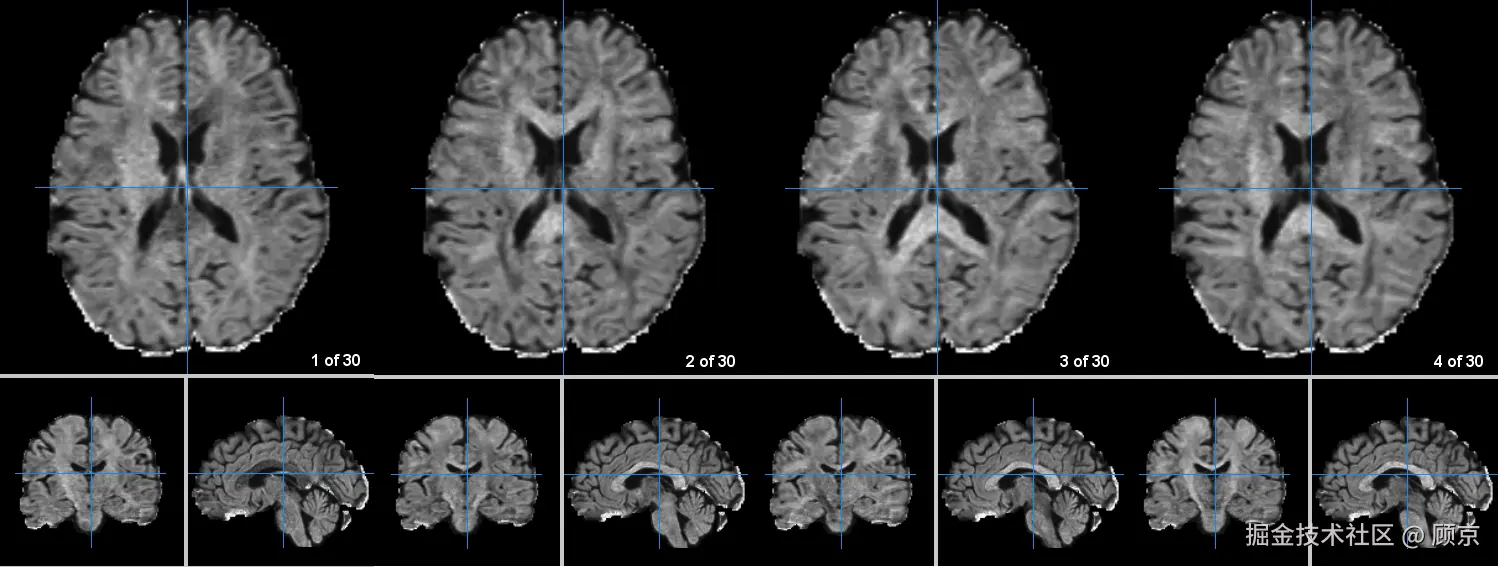

注意,dmri图像和noddi图像有采集方向的概念,一般用mango打开的话,一个slice就是一个方向。我现在的理解是为了测量水分子的扩散方向,于是从不同角度(通道)进行观察,就跟彩色图像的RGB通道一样,从不同视角观测同一个事物(可能比较肤浅,欢迎指正)。

不同方向的dmri结果.png

图4 不同方向的DMRI结果